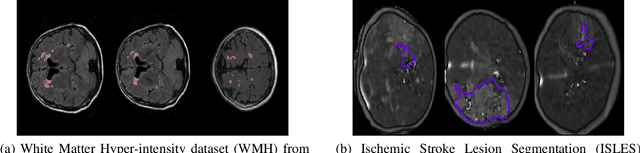

Abstract:Today, deep convolutional neural networks (CNNs) have demonstrated state-of-the-art performance for medical image segmentation, on various imaging modalities and tasks. Despite early success, segmentation networks may still generate anatomically aberrant segmentations, with holes or inaccuracies near the object boundaries. To enforce anatomical plausibility, recent research studies have focused on incorporating prior knowledge such as object shape or boundary, as constraints in the loss function. Prior integrated could be low-level referring to reformulated representations extracted from the ground-truth segmentations, or high-level representing external medical information such as the organ's shape or size. Over the past few years, prior-based losses exhibited a rising interest in the research field since they allow integration of expert knowledge while still being architecture-agnostic. However, given the diversity of prior-based losses on different medical imaging challenges and tasks, it has become hard to identify what loss works best for which dataset. In this paper, we establish a benchmark of recent prior-based losses for medical image segmentation. The main objective is to provide intuition onto which losses to choose given a particular task or dataset. To this end, four low-level and high-level prior-based losses are selected. The considered losses are validated on 8 different datasets from a variety of medical image segmentation challenges including the Decathlon, the ISLES and the WMH challenge. Results show that whereas low-level prior-based losses can guarantee an increase in performance over the Dice loss baseline regardless of the dataset characteristics, high-level prior-based losses can increase anatomical plausibility as per data characteristics.